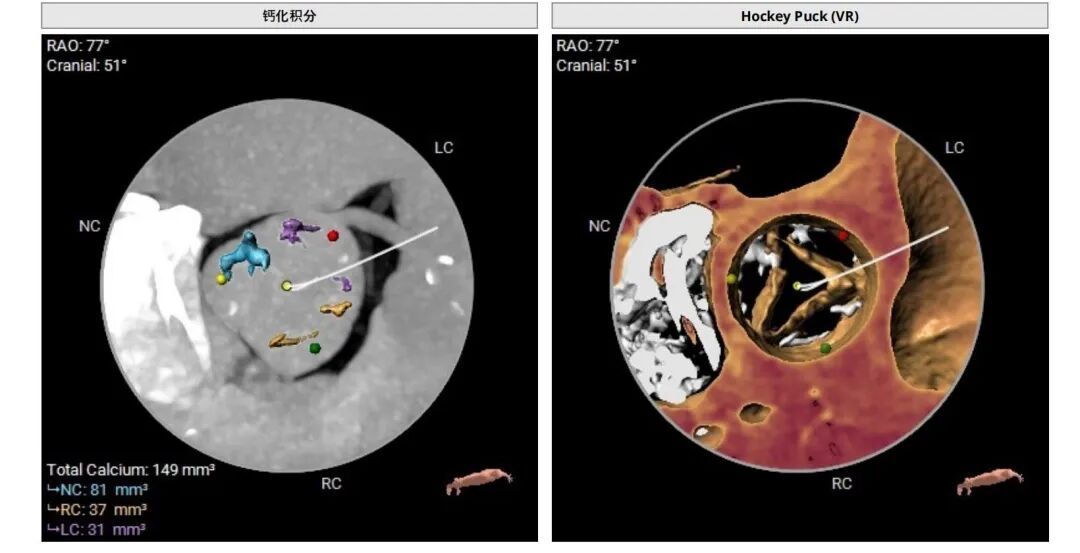

曾阿姨术前评估:轻度钙化,钙化积分共:149